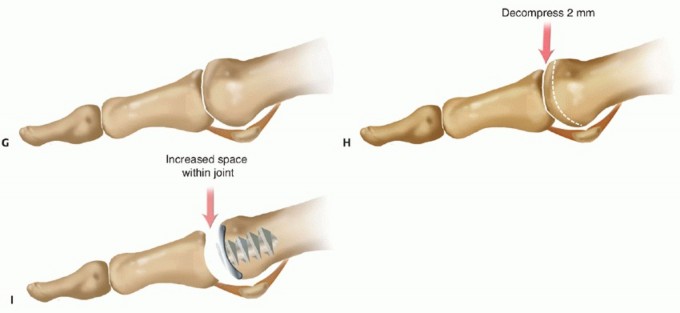

FIG 6 • A. Arthrosurface HemiCAP DF implant. B. Side view depicting implant design feature of dual radii of curvature along dorsal aspect. C. Change in radius curvature of implant creates additional space dorsally by receding slope.

One such implant is the Arthrosurface HemiCAP DF which is a second generation metatarsal head resurfacing implant. The “DF” signifies dorsal flange which provides improved dorsal coverage and prevents reformation of dorsal osteophytes occasionally seen in the original HemiCAP design. In addition, the implant was designed with a unique geometric feature to the dorsal slope of the head where a double radii of curvature was built in. At a point which corresponds to 12 degrees dorsiflexion, the radii of curvature changes effectively, creating built-in dorsal decompression to the implant. The purpose of the double radii is to improve what the senior author calls “passive dorsal roll back” of the proximal phalanx, as it clears and glides over the metatarsal head upon ambulation, thereby reducing the cam effect may expect in a contracted first MTP joint on weight-bearing dorsiflexion (FIG 6*). The HemiCAP DF more anatomically

matches the first metatarsal head morphology and was based on a biomechanical study which demonstrates

the center of rotation changes with varying degrees of dorsiflexion.19 The technique for the HemiCAP DF first metatarsal head resurfacing procedure is described in the following text.